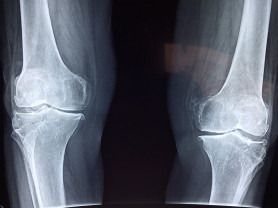

Az egészségügyi szakértő szerint a legdurvább az, hogy az akut baleseti ellátásban sem lehet csípőprotézissel megoperálni a combnyaktörést szenvedett betegeket.

Ha van a NEAK-nak 4-5 milliárd forintja arra, hogy lecsökkentse a várólistákat, akkor azt nem a protokollok ellenőrzésére kellene költeni – mondta Hegedűs Zsolt.